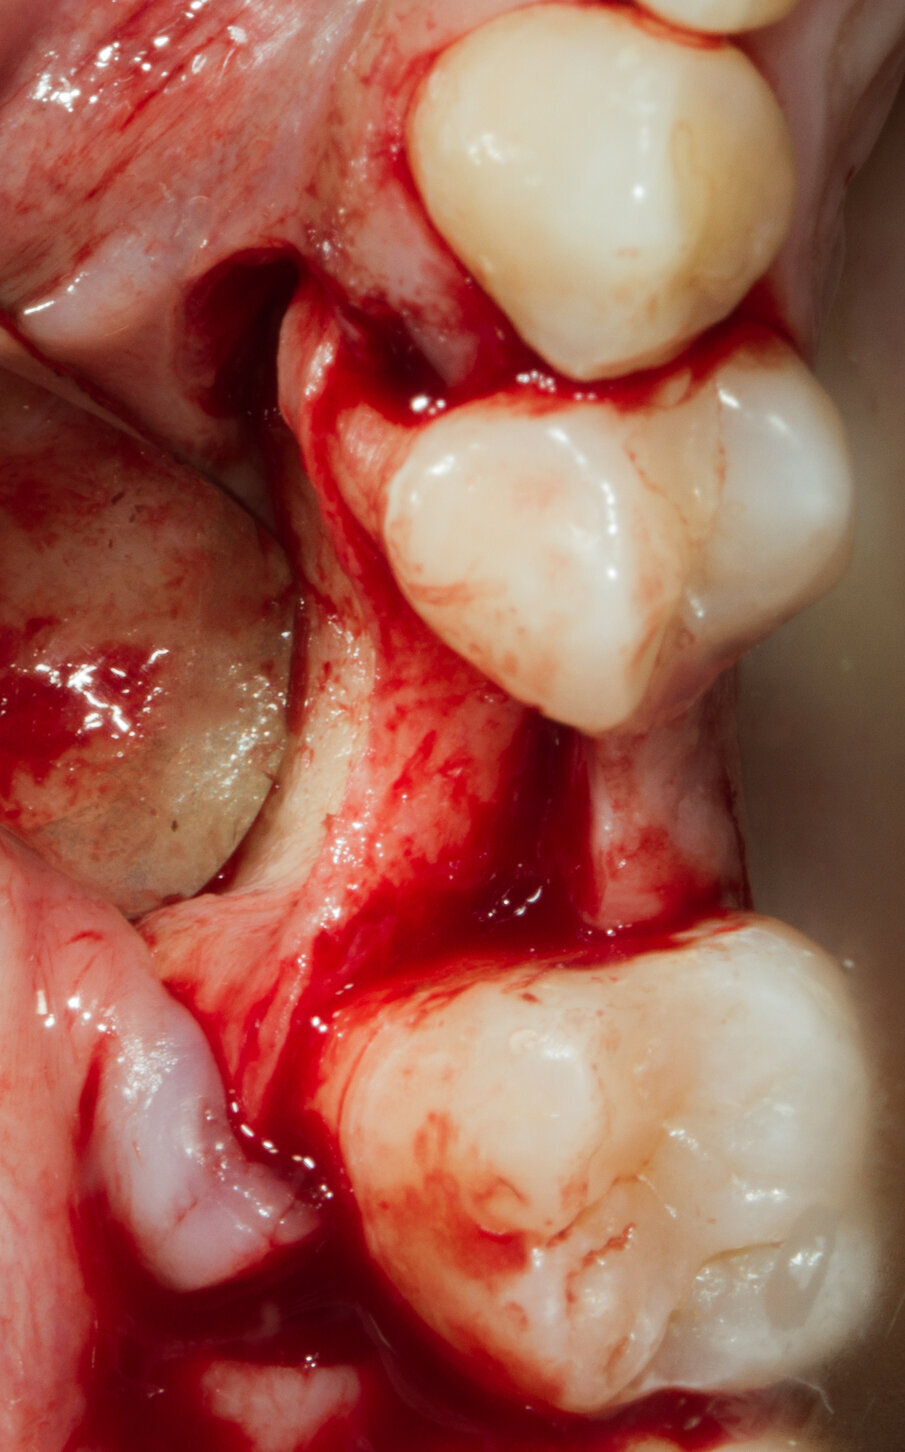

Si programma un intervento di GBR con rigenerazione ossea orizzontale mediante utilizzo di granuli di sostituto osseo eterologo (OsteoBiol Gen-Os) e un device riassorbibile costituito da osso corticale eterologo (OsteoBiol Lamina Soft). A 10 mesi verrà inserito un impianto differito. Dopo aver inciso un lembo mucoperiosteo con incisioni di scarico verticali e scollato sino alla parte più apicale del vestibolo si apprezza l’estrema sottigliezza della cresta residua e la sua corticalizzazione (Figg. 5, 6). Vengono praticati dei fori di 1,4 mm di diametro nella corticale vestibolare per esporre la midollare interna e aumentare la vascolarizzazione del particolato osseo che verrà innestato nel difetto osseo (Fig. 7).

Fig. 5 - Il marcato avvallamento osseo è presente in tutta l’altezza del vestibolo.

Fig. 6 - Visione crestale del difetto osseo.